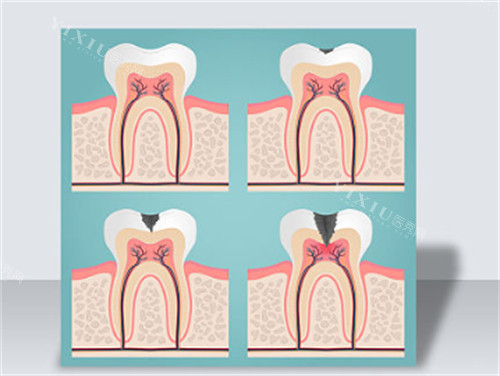

根管治疗(前牙):320 元起

根管治疗(后牙):500 元起